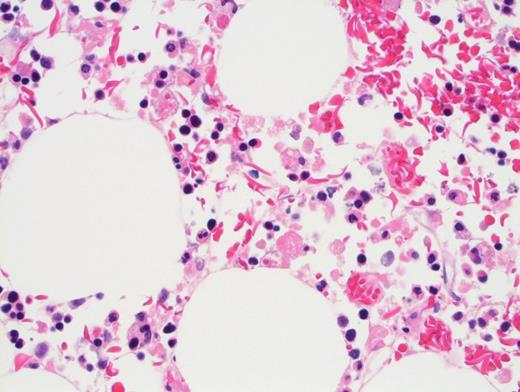

Peripheral blood showed abnormal red cell findings (Figure 1) with erythroblastosis (not shown). Aspirate showed trilineage hematopoiesis with erythroid predominance (Figure 2). Core biopsy showed hypercellular marrow (Figures 3 and 4) with focal areas of marrow damage (Figure 5). Hemoglobin high-performance liquid chromatography (HPLC) was performed (Figure 6).

The peripheral blood showed numerous target cells, burr cells, and microcytes, as well as partially sickled cells and blister-like cells. Core biopsy shows erythroid hyperplasia with large clusters of sickled cells (present in macrophages by CD68 stain; not shown).

The differential diagnosis for BMN/FES includes thrombotic thrombocytopenic purpura (TTP), HLH, and hyperhemolysis. That this patient’s platelet count was well above 30 × 109/L as well as an ADAMTS13 level of 61 percent ruled out TTP. The bone marrow was originally performed to investigate for HLH (given the markedly elevated ferritin). There were numerous hemophagocytic macrophages with engulfed sickle cells (confirmed by CD68 stain). However, this finding can be seen in the setting of sickle crisis without being associated with HLH disease. Aspirate smear and touch prep did not reveal prominent hemophagocytic macrophages as are typically seen in HLH. The presence of erythroblastosis also argues against HLH.

The presence of blister cells and low G6PD activity (hemoglobin, 4.7 U/g; reference range, 8.8-13.4 U/ g) also argues for a component of oxidative damage causing ongoing hemolysis for this patient.While there is an erythroid expansion with left shift (and pronormoblasts present), there is trilineage hematopoiesis with maturation. Pronormoblasts are not greater than 30 percent of cellularity. Therefore, this case does not meet criteria for pure erythroid leukemia.8